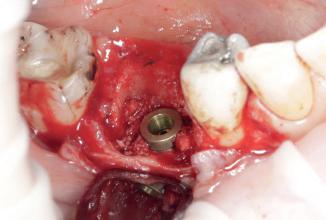

Synergy, as defined by the Cambridge Dictionary, is ‘the combined power of a group of things when they are working together that is greater than the total power achieved by each working separately’. When carrying out surgical procedures it is important that you use equipment solutions developed to offer a synergistic approach to your surgical processes. The equipment and instruments used should work in harmony to allow you to provide top quality treatment.

When it comes to synergy in dental implant procedures, such an approach often enables dental professionals to achieve better accuracy during the surgical phase. For instance, guided implant surgery utilises computer-generated surgical guides to enhance the precision of implant placement. By combining 3D imaging technology with specialised surgical instruments, dental clinicians are able to carefully plan the position, angle, and depth of the dental implant prior to the actual surgery. This collaborative effort between advanced imaging software and specialised instruments ensures that the implant is placed precisely in the desired location, leading to better aesthetic outcomes and increased patient satisfaction.

Seamless integration

Another advantage of instrument synergy in dental implant procedures is the reduced risk of surgical complications. Using specially designed surgical instrument and handpieces, allow dentists to ensure that they have everything necessary and readily available during a procedure. This allows the dental team to work efficiently and

effectively. The benefits of using compatible handpieces and equipment ensures that they can be seamlessly integrated into the surgical workflow, further reducing the time required for the procedure.

Seamless integration of instruments in dental implant procedures can also improve patient comfort and reduce recovery time. Advanced technology, such as piezoelectric instruments using ultrasound technology, offers precise and controlled cutting of bone, minimising trauma to the surrounding tissues. This means that patients experience less pain, swelling and bruising post-surgery, leading to a quicker and more comfortable recovery. Additionally, the combined use of specialised instruments, such as tissue punches and implant placement tools, allows for minimally invasive techniques that preserve the integrity of soft tissues. By reducing damage to the surrounding structures, patients experience less post-operative discomfort and achieve quicker healing.

clinical toolkit. Utilising the Piezomed improves procedure outcomes and results for patients as it is gentle on soft tissue ensuring reduced patient discomfort and quicker healing. For those placing implants measurement of osseointegration is ideal as it allows them to monitor the dental implants to inform loading decisions and ensure success. The Osstell Beacon from W&H, gives dental professionals peace of mind as they can measure and evaluate the stability of the implant ensuring full osseointegration, helping to reduce treatment times and avoid rejection in high-risk patients.

Working with equipment and instruments from top quality suppliers like W&H, who offer a highly synergistic approach based on many years of research, development and surgical know-how, allows for the best possible treatment outcomes. The Piezomed provides dental professionals with the benefits of innovative piezosurgery. By using the high-quality system, clinicians can remove only the targeted bone with precision, leaving the surrounding soft tissue and bone undamaged. The Piezomed module integrates seamlessly with the Implantmed Plus surgical unit, this flexibility between the Implantmed with surgical handpieces and the Piezomed creates a superior workflow driven solution for oral surgery, guiding the clinician through the cycle from implementation to evaluation. With W&H’s synergistic approach, which includes the use of the Implantmed, with the range of surgical handpieces, alongside the Piezomed the dentist benefits from an incredibly versatile

Overall, a synergistic solution to dental implant procedures offers numerous advantages that enhance the overall success of these procedures. Patient comfort is improved through the use of advanced instruments that minimise trauma and promote faster healing. With these advantages in mind, it becomes clear that dental implant procedures require wellthought through planning and the correct equipment. This helps to develop a solution which allows the clinician to provide high quality treatment enabling them to deliver patients with effective, efficient, and longlasting solutions for missing teeth.